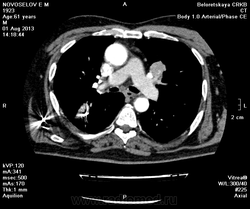

Мужчина оперирован по поводу BL щитовидной железы.Неоднократно проходил КТ в других лечебных учреждениях, у нас- впервые.Ставились заключения:MTS в лёгкие и лимф.узлы средостения слева.Образование слева увеличилось.Жалуется на одышку, не верит в заключение о MTS,просит узнать мнение других специалистов.

Метастазов в легкие не вижу. Похоже на лимфоузел в головке левого корня. Если позволите, запаздываете с началом исследования, плотность контраста в легочных артериях должна быть выше, чем а аорте. А одышка, не мудрено, легочная ткань диффузно уплотнена по типу "матового стекла", написал бы какую-нибудь интестициальную пневмонию, по типу альвеолита, может быть и гиперчуствительный пневмонит (не разберу есть или нет внутридольковые очажки), посмотреть бы изначально легочное окно, а не восстановленное из мягкотканного.

Коллега, вынужден извинться и дезавуировать свой первый пост. Пересмотрел. Да, есть очаги, и они - вероятнее всего, метастазы.

Единственное,что напрягает,так это то,что эти изменения у пациента более 1,5 лет.А вид внешний у него не так уж и плох.А слева это всё-таки лимфоузел, а не периферическое образование в S3?

Думаю, да. Слишком близко лежит к легочной артерии.